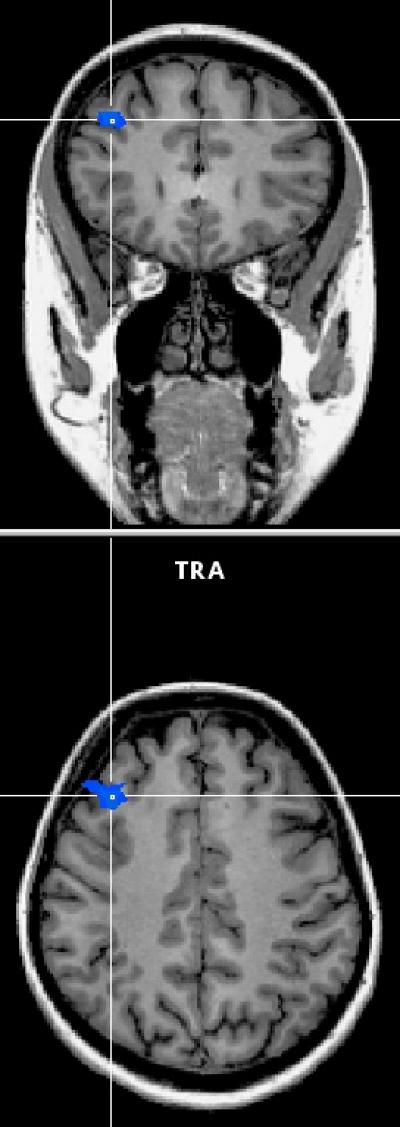

But Hedgcock's study is the first to actually show it happening in the brain using fMRI images that scan people as they perform self-control tasks. The images show the anterior cingulate cortex (ACC)—the part of the brain that recognizes a situation in which self-control is needed and says, "Heads up, there are multiple responses to this situation and some might not be good"—fires with equal intensity throughout the task.

However, the dorsolateral prefrontal cortex (DLPFC)—the part of the brain that manages self-control and says, "I really want to do the dumb thing, but I should overcome that impulse and do the smart thing"—fires with less intensity after prior exertion of self-control.

He said that loss of activity in the DLPFC might be the person's self-control draining away. The stable activity in the ACC suggests people have no problem recognizing a temptation. Although they keep fighting, they have a harder and harder time not giving in.

The researchers gathered their images by placing subjects in an MRI scanner and then had them perform two self-control tasks—the first involved ignoring words that flashed on a computer screen, while the second involved choosing preferred options. The study found the subjects had a harder time exerting self-control on the second task, a phenomenon called "regulatory depletion." Hedgcock says that the subjects' DLPFCs were less active during the second self-control task, suggesting it was harder for the subjects to overcome their initial response.